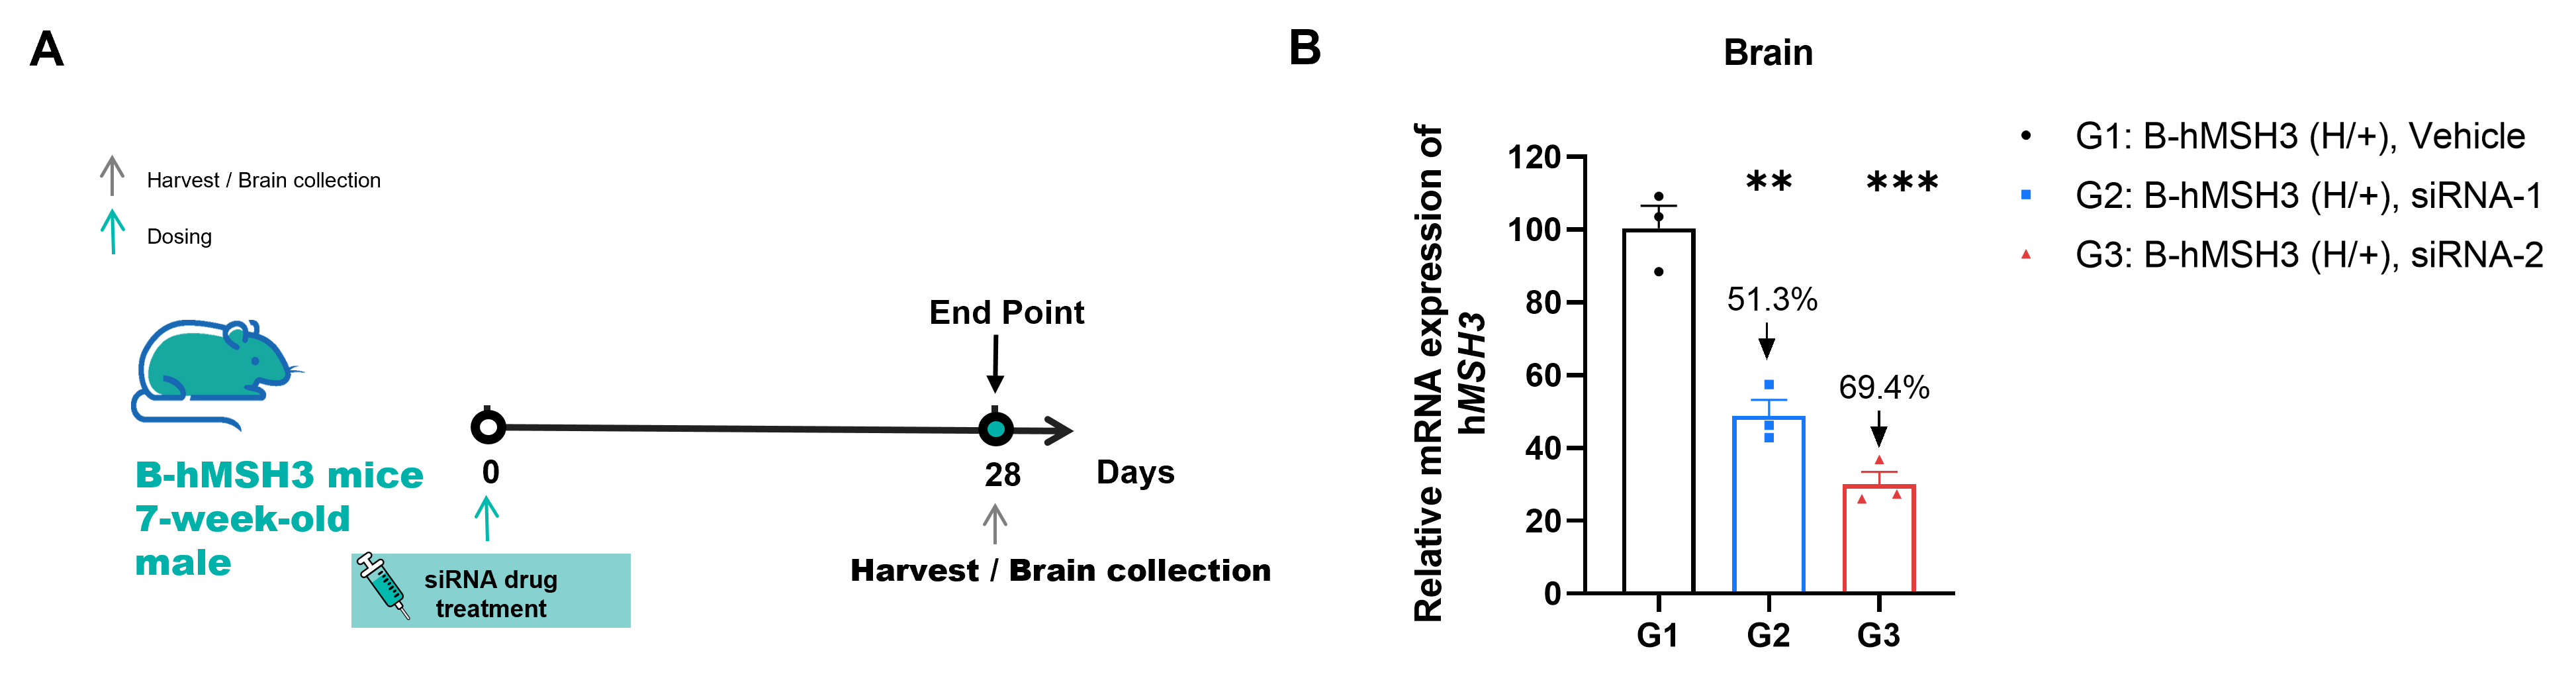

The inhibitory efficiency of the MSH3-targeted small nucleic acid drug in heterozygous B-hMSH3 mice. B-hMSH3 mice were randomly divided into 3 groups (n=3, 7-week-old, female). The human MSH3-targeted nucleic acid drug were administered to the mice individually. The mice were sacrificed on day 28, and the brains were collected to detect the human MSH3 expression by qRT-PCR. (A) The schematic diagram of experimental processing. (B) The expression of human MSH3 mRNA in brain from different groups. The human MSH3 mRNA in the treatment group was significantly reduced compared to the control group. Values are expressed as mean ± SEM. Significance was determined by unpaired t test. *P < 0.05, **P < 0.01, ***P < 0.001.